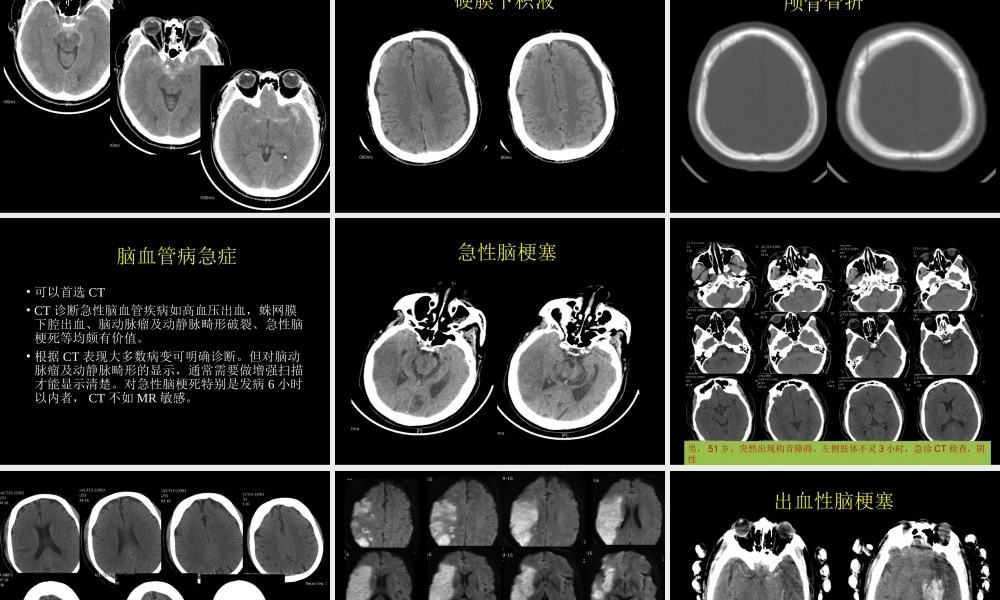

急症影像学检查与诊断中国石油中心医院杨景震急症的影像检查与诊断范畴非常广泛,涉及内、外、妇、儿等临床学科,急症病员病情急重,变化迅速。及时而正确的影像学检查与诊断直接影响病人的治疗及预后。急症常用的影像检查设备•直接数字化摄影系统(DR)•多排螺旋CT•数字X光胃肠机•MRI急症影像学常见疾病•颅脑:脑血管疾病、颅脑外伤、感染性疾病、急性静脉窦栓塞等。•胸部:食管、支气管异物、胸部外伤、急性肺梗塞、肺炎、自发性气胸等。•腹部:消化道穿孔、肠梗阻、肠套叠、急性胰腺炎、胆囊炎、尿路结石、急性阑尾炎、腹部创伤、盆腔疾病等。•脊柱:外伤、椎体骨折、脊髓损伤。•四肢关节:骨折、脱位等。•大血管疾病:主动脉夹层等。创伤性颅脑急症影像学诊断•首选CT检查•CT在创伤性颅脑急诊诊断中属常规和首选检查方法,可清楚显示脑挫裂伤、急性脑内血肿、硬膜下及硬膜外血肿、颅面骨骨折、颅内金属异物等。脑挫裂伤•脑挫裂伤是指颅脑外伤所致的脑组织器质性损伤,是最常见的颅脑外伤之一。•多发生于着力点及其附近,也可发生于对冲部位,常并发蛛网膜下腔出血。•病理改变包括脑外伤引起的局部脑水肿、坏死、液化和多发散在小出血等变化。•临床表现有伤后头痛、恶心、呕吐和意识障碍。硬膜外血肿•颅脑出血积聚于颅骨与硬膜之间,称为硬膜外血肿。•约占各种颅脑外伤血肿的1/3,多为急性或亚急性,慢性少见。•损伤局部多有骨折,因硬膜与颅骨粘连紧密,故血肿范围局限,形成双凸透镜形。硬膜下血肿•颅内出血积聚于硬脑膜与蛛网膜之间称为硬膜下血肿。•根据血肿形成时间可分为急性(3天之内)、亚急性(3天~3周)和慢性(3周以上)。•硬膜下血肿常与脑挫裂伤同时存在,血肿居于脑凸面硬膜与蛛网膜之间,形状多呈新月或半月形,血肿范围较大,可掩盖整个大脑半球。•慢性硬膜下血肿的临床特点是有轻微头部外伤或没有明确的外伤史,经过至少3周以上时间逐渐出现颅内压增高和脑压迫症状。蛛网膜下腔出血•是指颅内血管破裂后血液进入蛛网膜下腔所致。•临床可分为外伤性、自发性。•主要症状:有明显的外伤史或突然发病,有明显诱因,出现突发性剧烈头痛、呕吐、意识障碍、抽搐、脑膜刺激征等。硬膜下积液颅骨骨折脑血管病急症•可以首选CT•CT诊断急性脑血管疾病如高血压出血,蛛网膜下腔出血、脑动脉瘤及动静脉畸形破裂、急性脑梗死等均颇有价值。•根据CT表现大多数病变可明确诊断。但对脑动脉瘤及动静脉畸形的显示,通常...